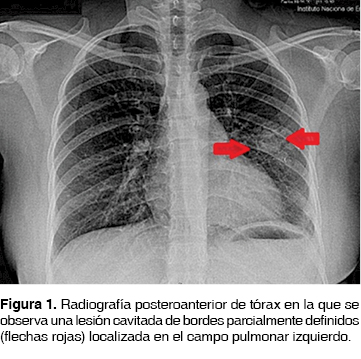

La mayoría de los pacientes presentan tos productiva con esputo mucoso, purulento e incluso hemoptoico.4 La actividad de las endotoxinas fúngicas, así como la fricción entre la "bola de hongos" y las paredes de las cavidades causan erosión vascular desencadenando hemoptisis, que en ocasiones es severa y fatal. La disnea en estos pacientes generalmente resulta de la enfermedad pulmonar previa.5 Radiológicamente se presenta de manera típica como una lesión cavitada de paredes gruesas, ocupada por contenido sólido, pudiendo estar asociada a cambios focales en el parénquima adyacente (figuras 1 y 2).